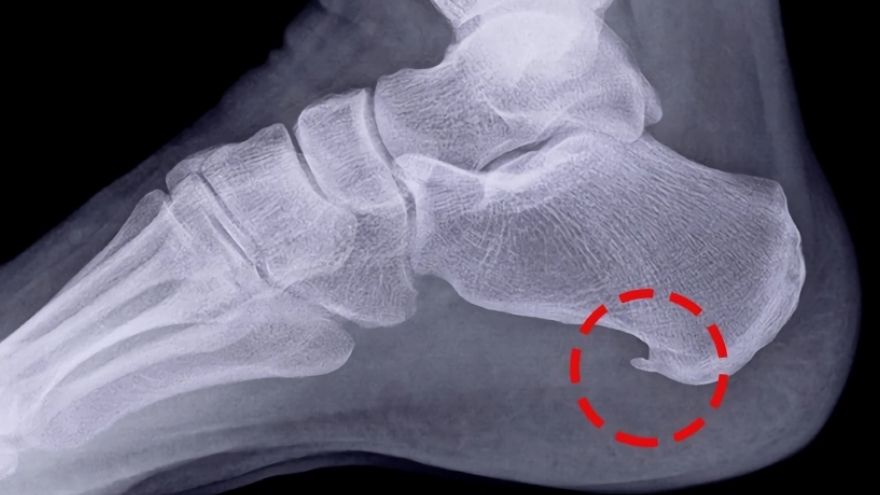

Tıptaki adı plantar fasit olan topuk dikeni, topuk kemiğinin altında, ayak tabanında yer alan ‘plantar fasya’ adı verilen bağ dokusunun iltihaplanması sonucu oluşan bir durumdur. Bu durum uzun süre devam ettiğinde topuk kemiğinde kalsiyum birikmesi meydana gelir ve röntgende diken şeklinde bir çıkıntı görülür. Bu durum halk arasında ‘topuk dikeni’ olarak adlandırılır.

Ayak kemiği sürekli strese maruz kaldığında topuk kemiği altında kireçlenme oluşur. Günlük yaşamda bu durumun etkisi yoktur fakat stres faktörlerine sürekli maruz kalınırsa topuk kemiğinin alt kısmı diken benzeri bir şekilde çıkıntı yapar. Bu çıkıntının sebebi ise topuk kemiğindeki tendonda yangı meydana gelmesi ve kemiğe tutunduğu bölgesinin sertleşerek kemikleşmesidir. Şişmanlık, düztabanlık, sert ve düz tabanlı ayakkabı ile yüksek topuklu ayakkabı giymek topuk dikeni riskini arttıran faktörlerdendir.